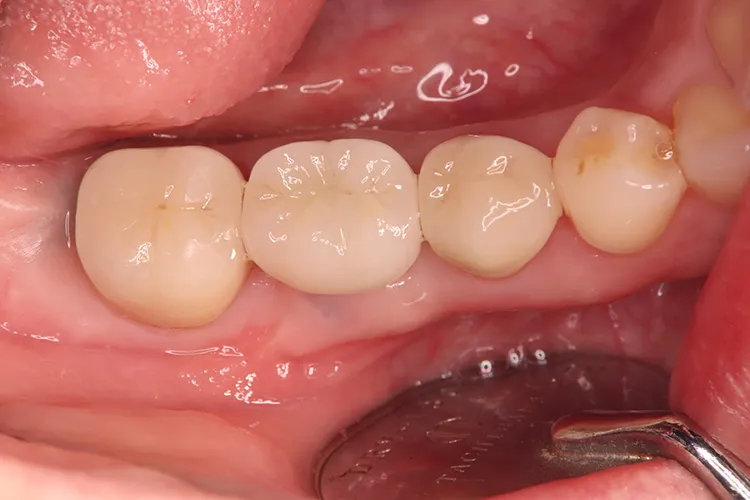

左下5本欠損した部分をインプラント3本埋入して5本ブリッジで治したケースです。なかなかインプラントに踏み切れず、長い間入れ歯を使っておられましたが、噛みごたえがなく好きなものが食べれない上に、度々歯茎が痛んでは調整の繰り返しで快適に過ごすことができず、QOLの向上のためインプラント治療を決断されました。今ではなんでも食べれるとのことで、入れ歯で我慢しないでもっと早くインプラントにすればよかったと言っておられます。